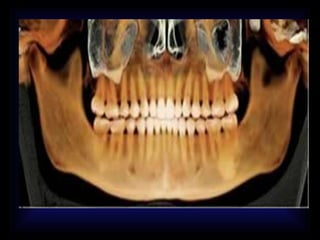

RADIOGRAFIAS DX ODONTOLOGICO •ANTERO POSTERIOR • A.P DE TOWNE • A.P. DE WATERS • PROYECCIONES LATERALES • PROYECCION A. DE CADWELL • PANORAMICA • PERIAPICAL • R.BITE WING